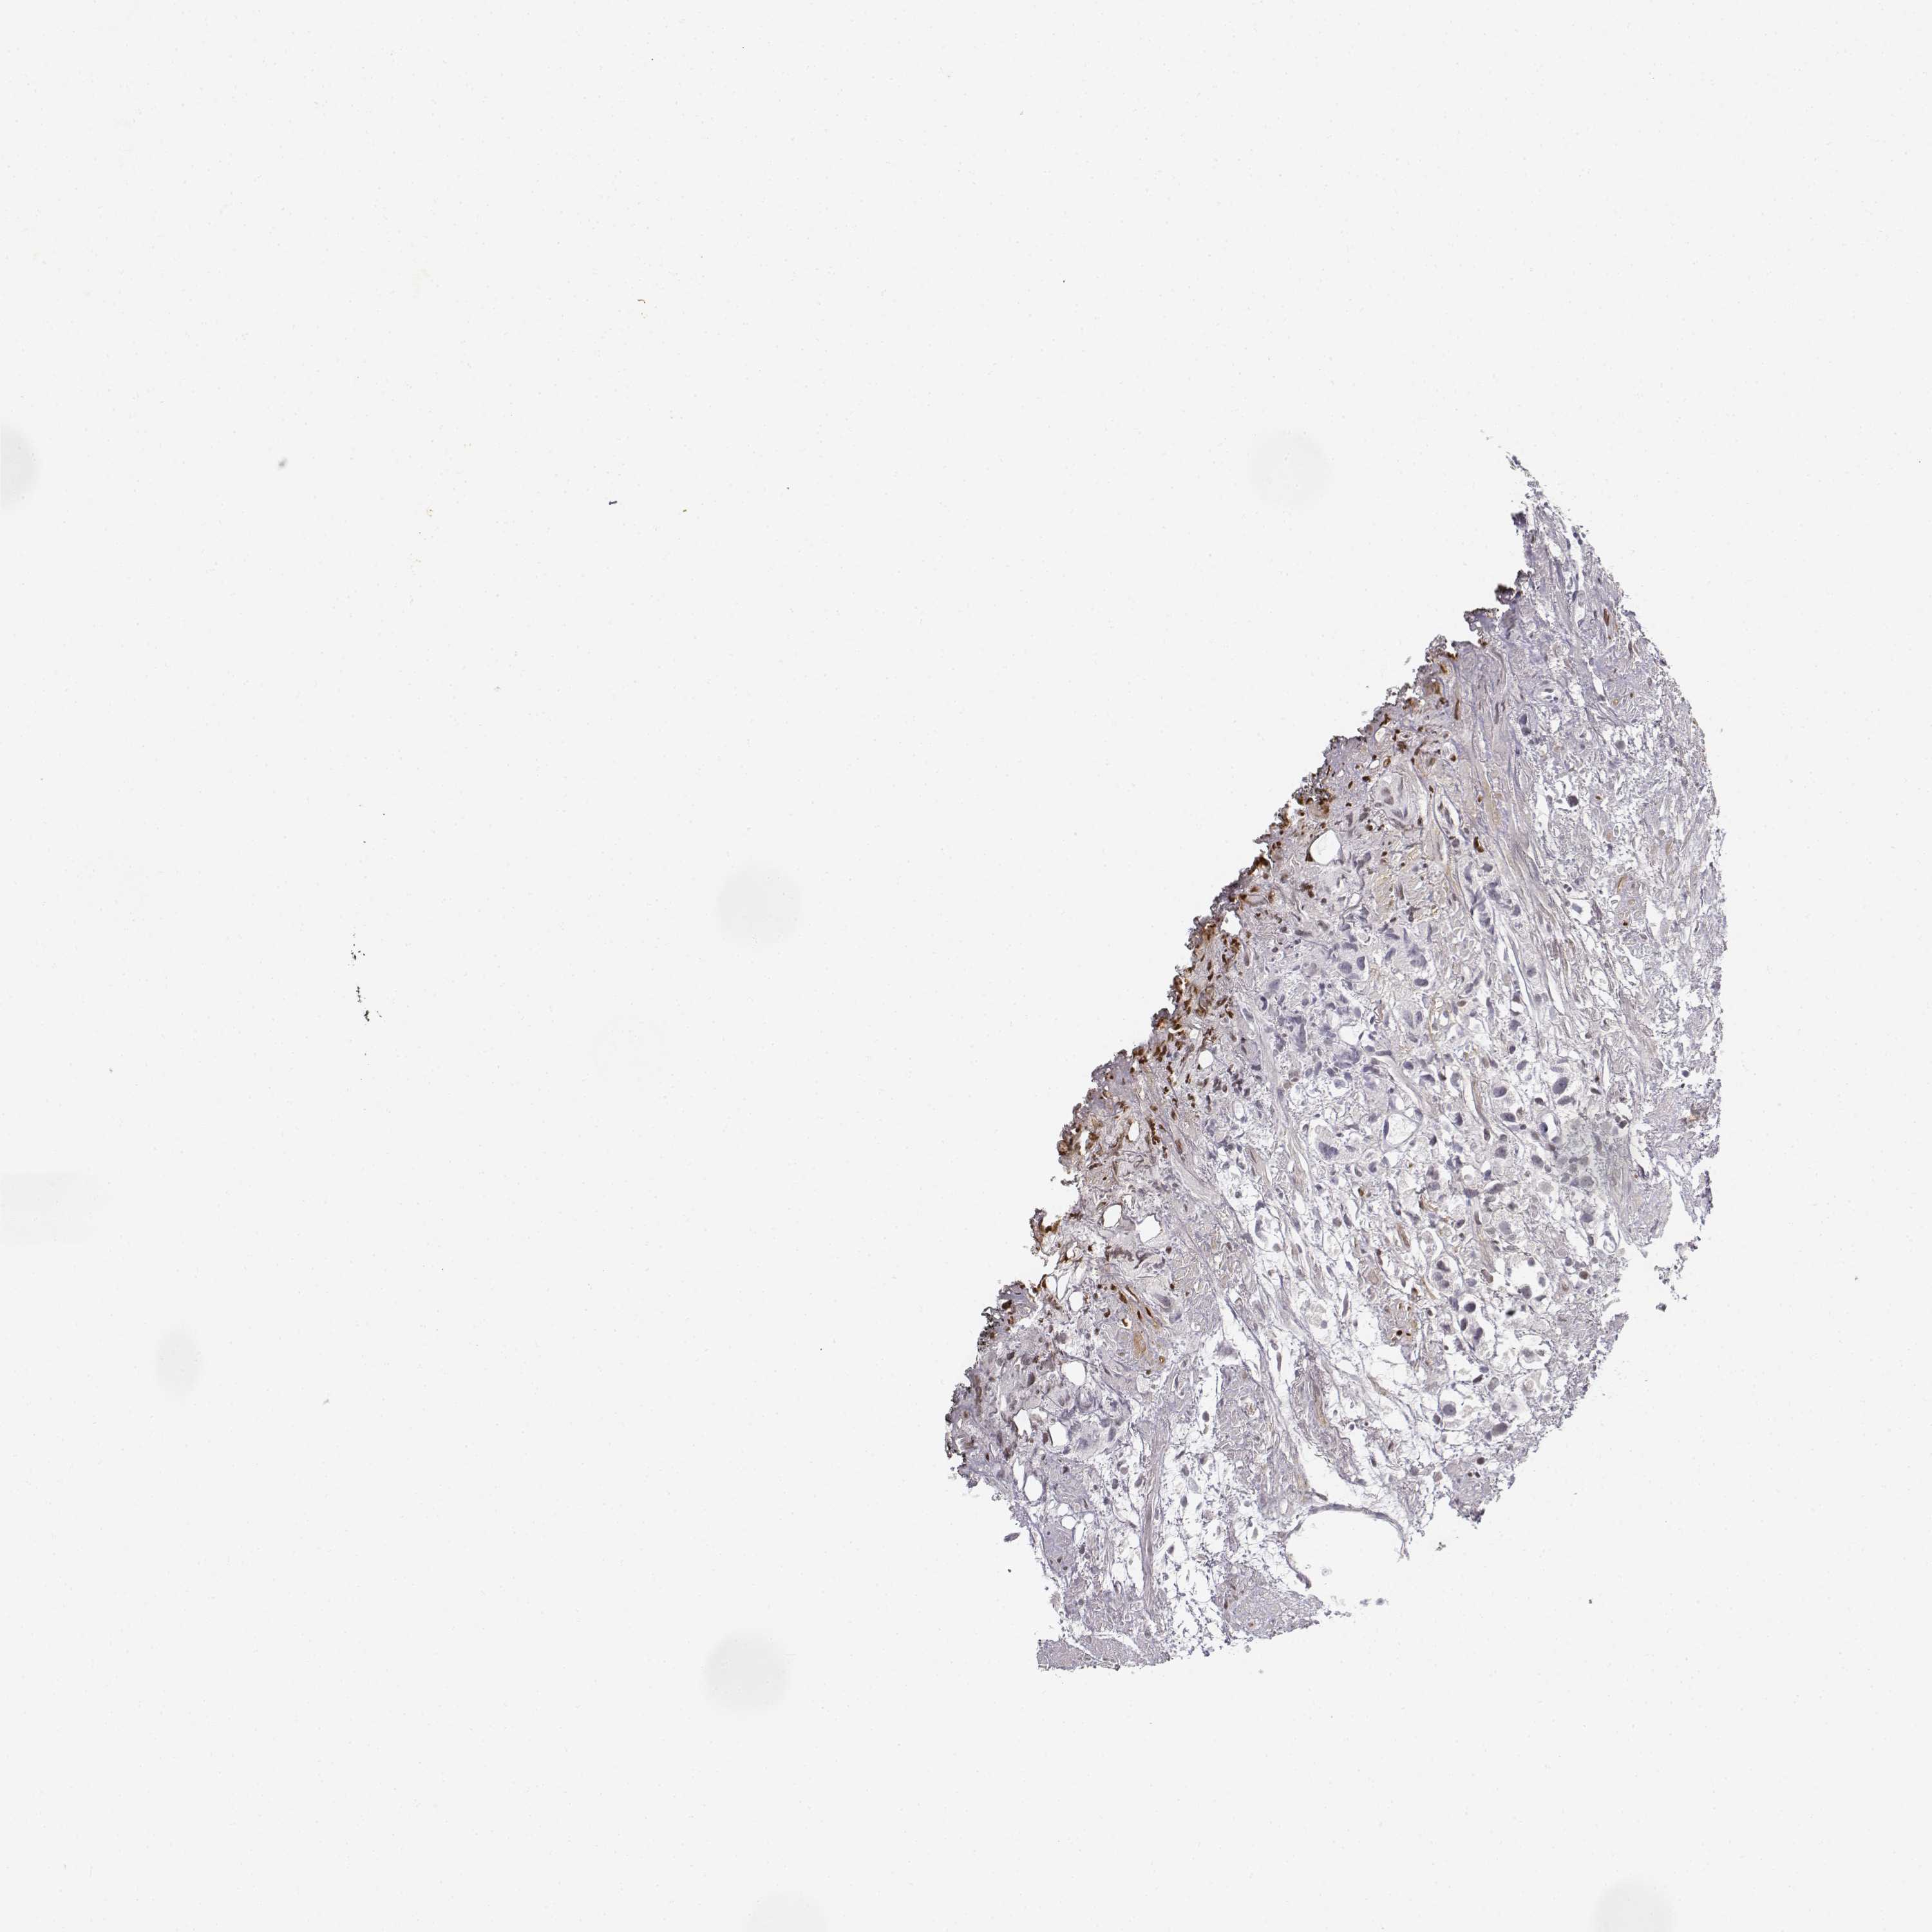

PROSTATE CANCER - Protein expressioni

A mouse-over function shows sample information and annotation data. Click on an image to view it in a full screen mode. Samples can be filtered based on level of antibody staining by selecting one or several of the following categories: high, medium, low and not detected. The assay and annotation is described here.

Note that samples used for immunohistochemistry by the Human Protein Atlas do not correspond to samples in the TCGA dataset.

Antibody stainingi

Antibody staining in the annotated cell types in the current human tissue is reported as not detected, low, medium, or high, based on conventional immunohistochemistry profiling in selected tissues. This score is based on the combination of the staining intensity and fraction of stained cells.

Each image is clickable and will lead to virtual microscopy that enables deeper exploration of all samples and also displays staining intensity scores, fraction scores and subcellular localization as well as patient and tissue information for each sample.

Antibody HPA039714

Staining

High

Medium

Low

Not detected

Intensity

Strong

Moderate

Weak

Negative

Quantity

>75%

75%-25%

<25%

None

Location

Nuclear

Cytoplasmic/membranous

Cytoplasmic/membranous,nuclear

Adenocarcinoma, High grade

Adenocarcinoma, NOS

Adenocarcinoma, Low grade